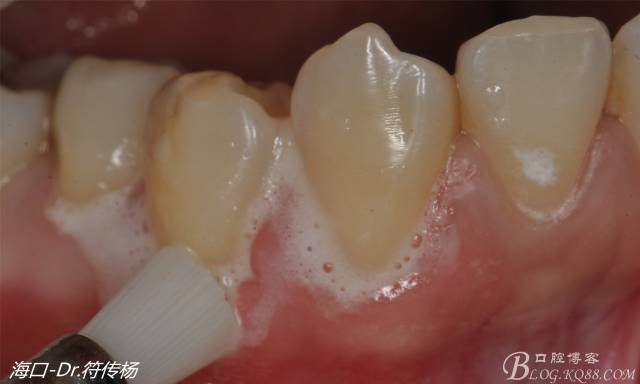

從病例圖片我們可以看到44牙頰側(cè)牙齦出現(xiàn)明顯萎縮

我們首先需要使用拋光刷+拋光膏清潔根面

然后使用EDTA處理根面2min利于牙周附著(有爭議)